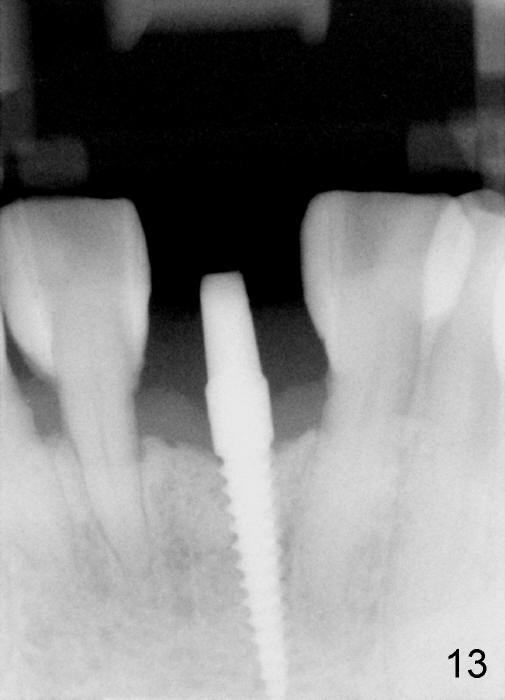

Fig.10,11 show 7 day follow up. The permanent crown is seated 4.5 months postop (Fig.12). Minimal bone resorption occurs at the crest 4 months postop (Fig.13), which is most likely associated with conservative approach (flapless). The patient returns for follow up 2.5 months post cementation (Fig.14,15). The implant remains in the bone 4 years post cementation (Fig.16 CT coronal section; lingual thread exposure, corresponding to preop defect in Fig.1). There is mild coronal bone resorption 5 years 4 months post cementation (Fig.17).